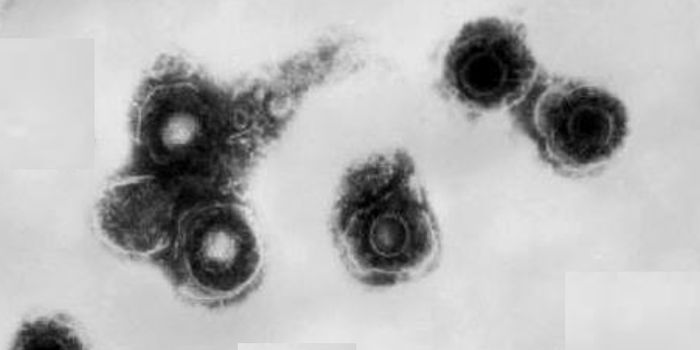

MAY 05, 2017CancerIt’s estimated that nine out of ten people are infected with the Epstein-Barr virus (EBV). The virus stays dormant ...

MAY 02, 2018ImmunologyThe measles virus was caught leaving infected cells by the scientific paparazzi, that is, experts from Emory Health Scie ...